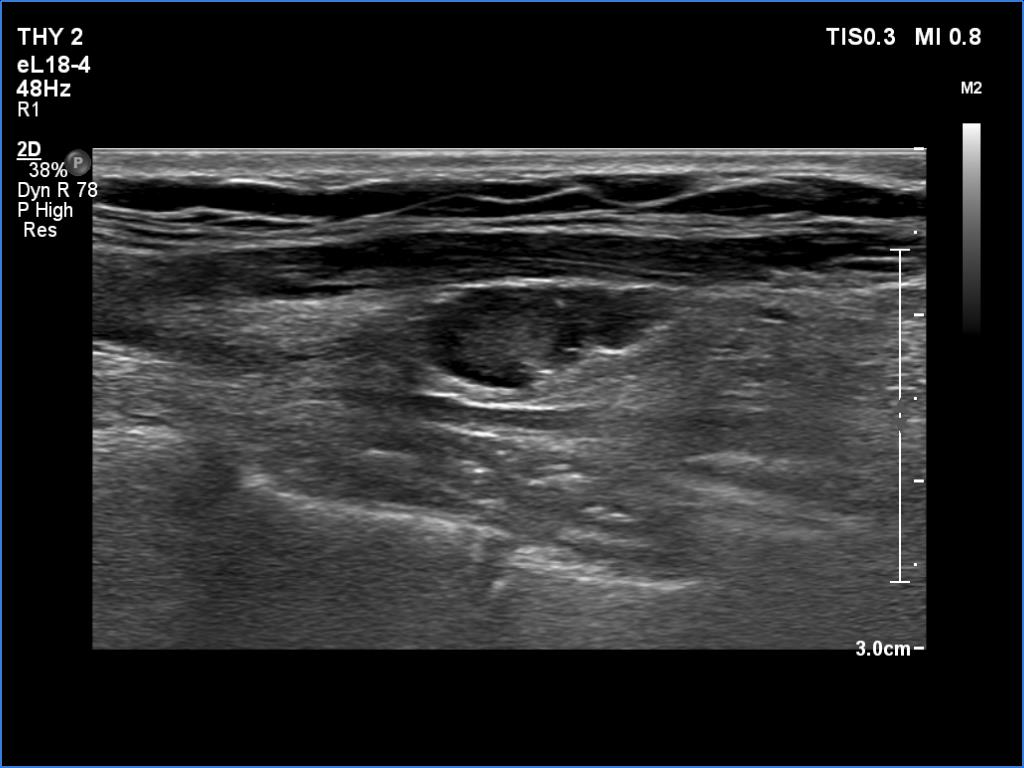

Ultrasonography. The right lobe was replaced with connective tissue. A hypoechoic mass was found in the left thyroid bed. On certain sections, this mass was very similar to a muscle fiber, however some other sections proved the presence of intralesional echogenic figures; the presence of back wall cystic figures was obvious but in the event of some granules microcalcifications should be considered. The lesion was vascularized, which excluded that the mass is muscle fiber.